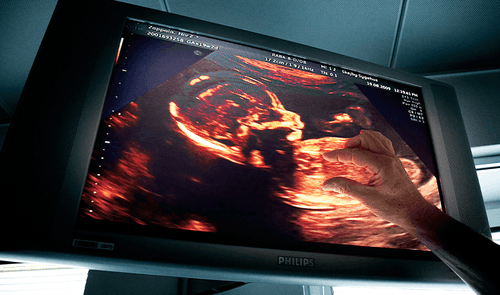

- Det er også muligt at hjælpe befrugtningen på vej ved hjælp af den såkaldte IVF-metode (In Vitro Fertilisation). Her starter man med at stimulere kvindens produktion af æg ved hjælp af hormoner. Lige før kvindens ægløsning, udtages de modne æg fra kvinden, hvorefter de befrugtes i en glasskål, ved at ægget tilføres 50.000-100.000 sædceller. To til fire døgn senere indføres et til to befrugtede æg i kvindens livmoder.